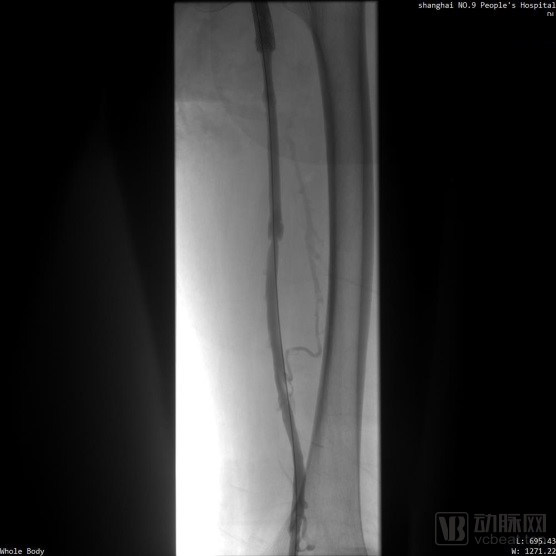

取栓術前管腔造影

取栓術後管腔造影

※ LuVoCaptor取栓前後管腔造影對照: